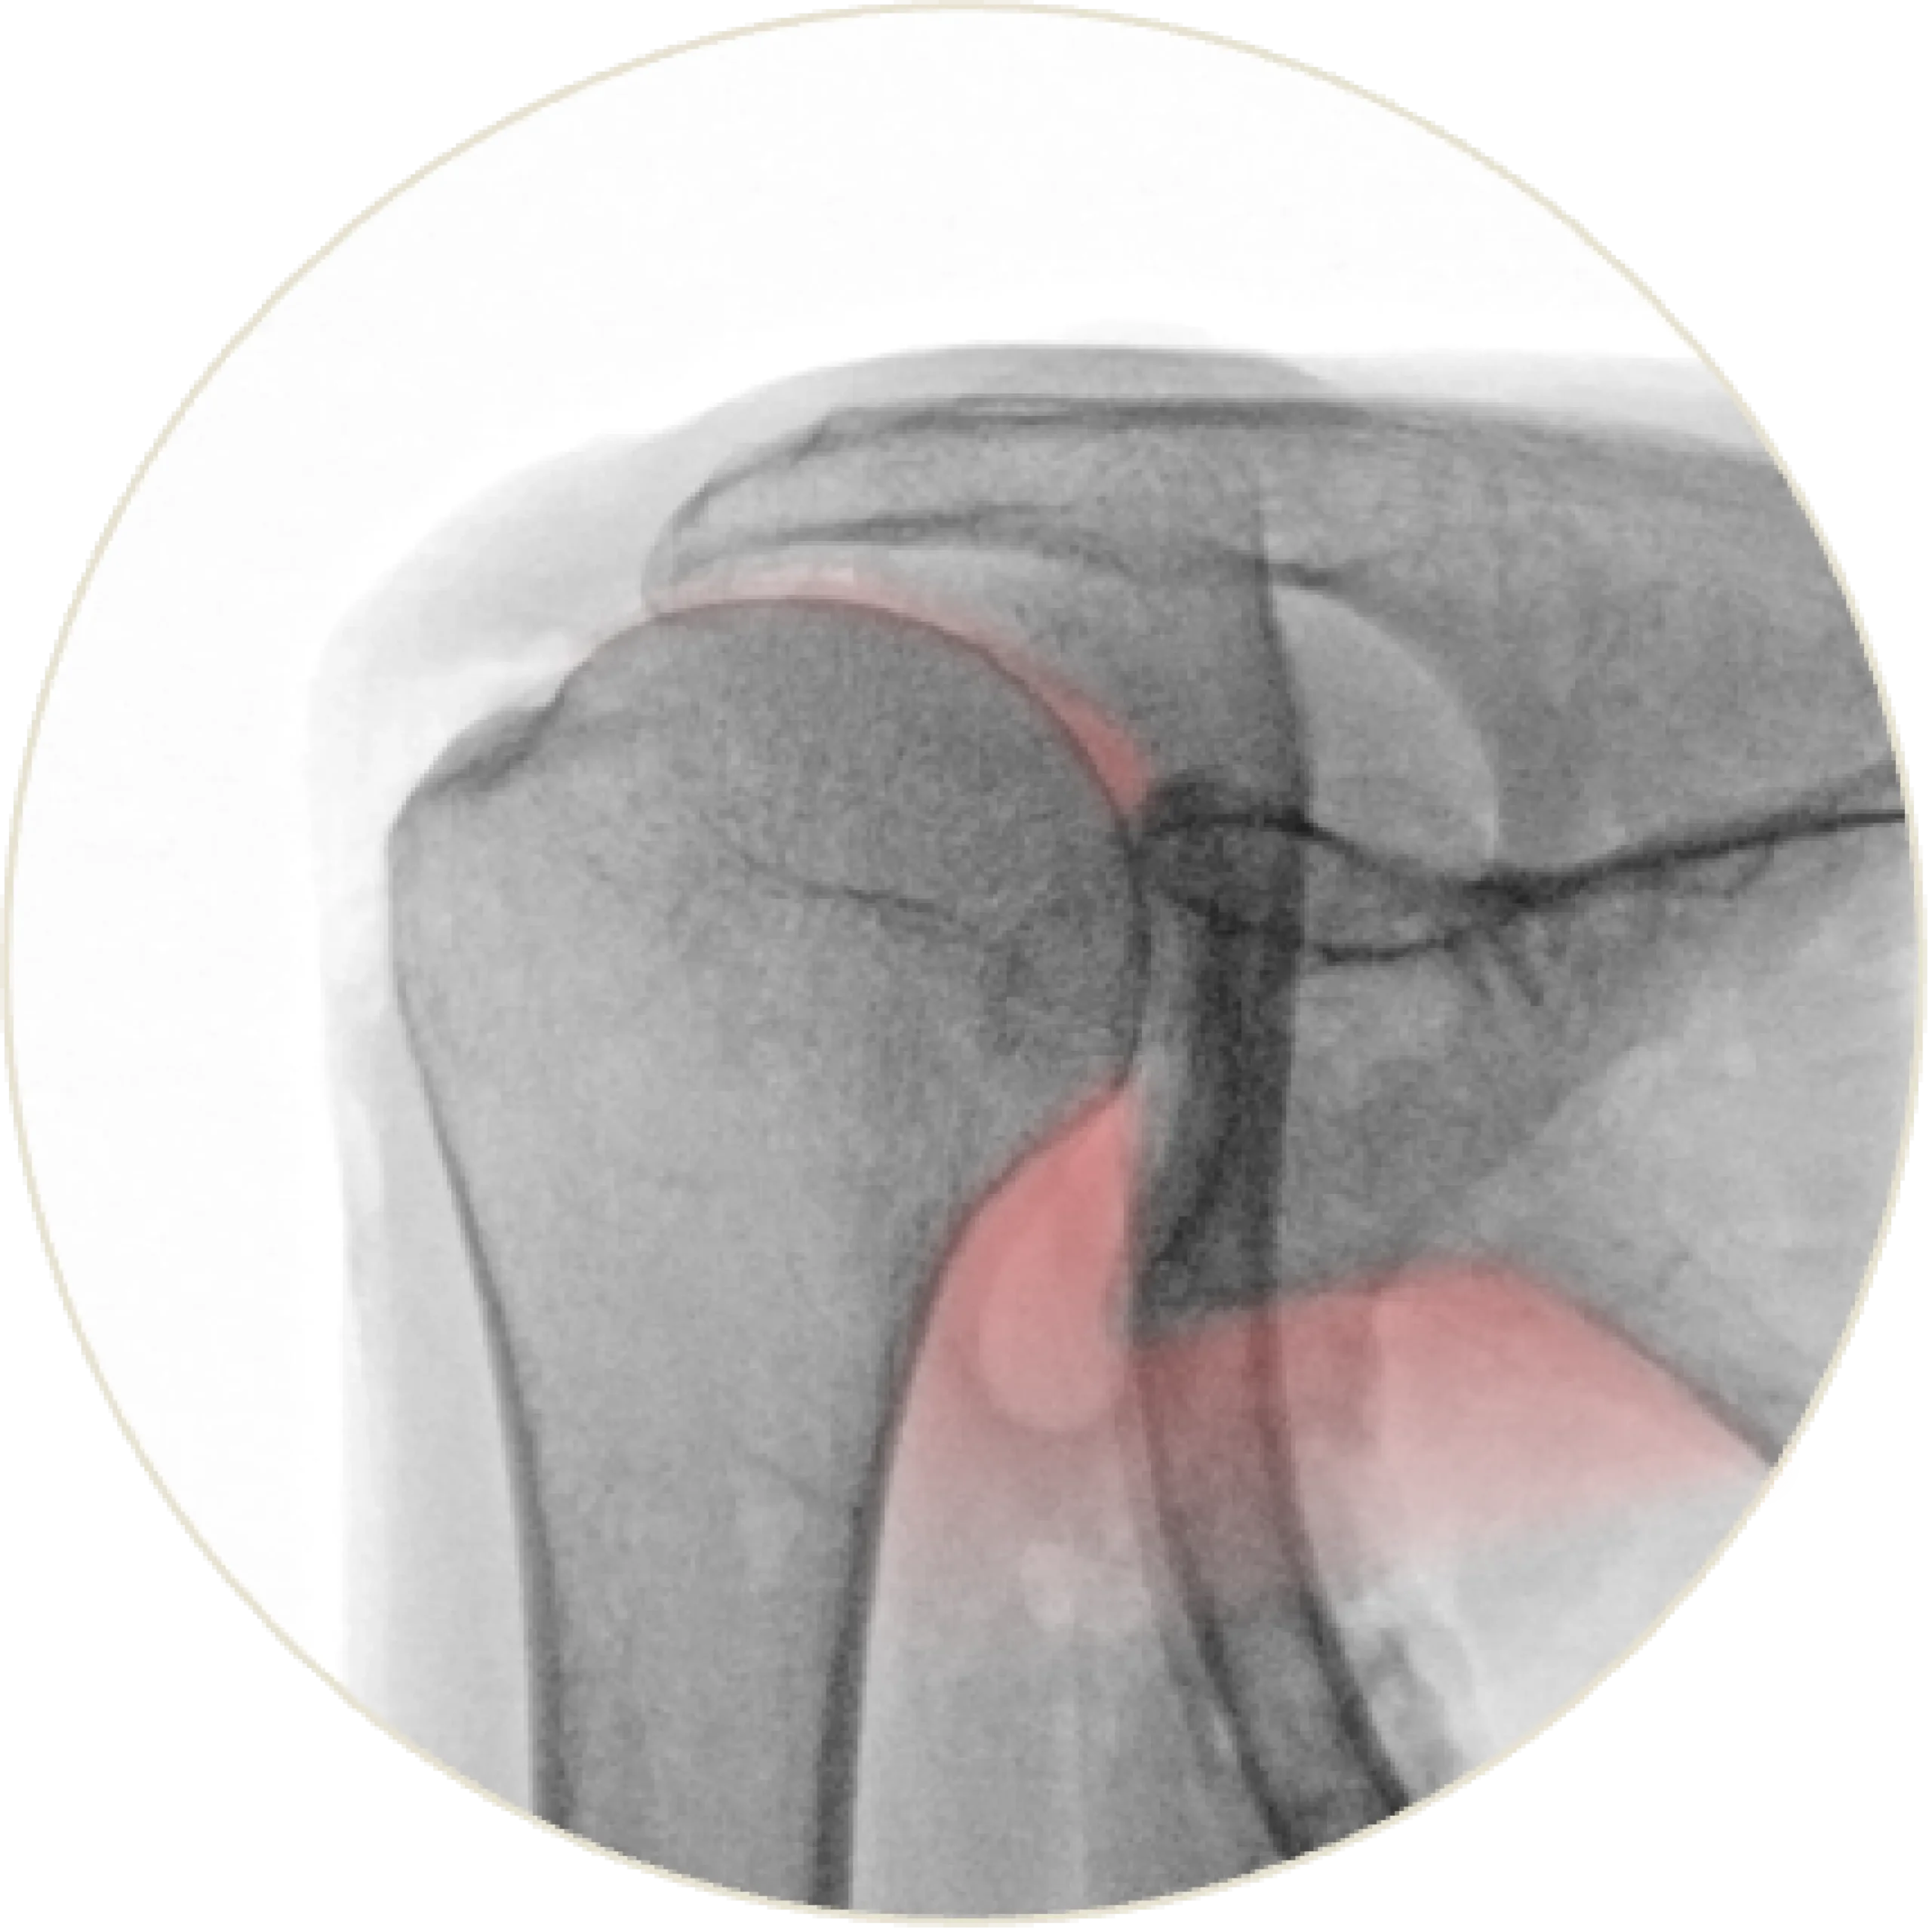

SupraSpacer™

The SupraSpacer™ restores anatomical spacing and natural joint alignment, allowing smooth articulation. It reduces impingement-related discomfort and supports balanced shoulder mechanics.